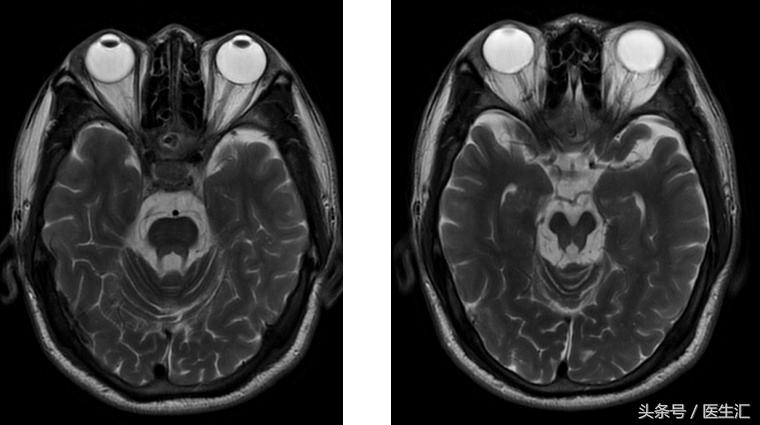

图像资料

核磁:小脑萎缩、脑干萎缩